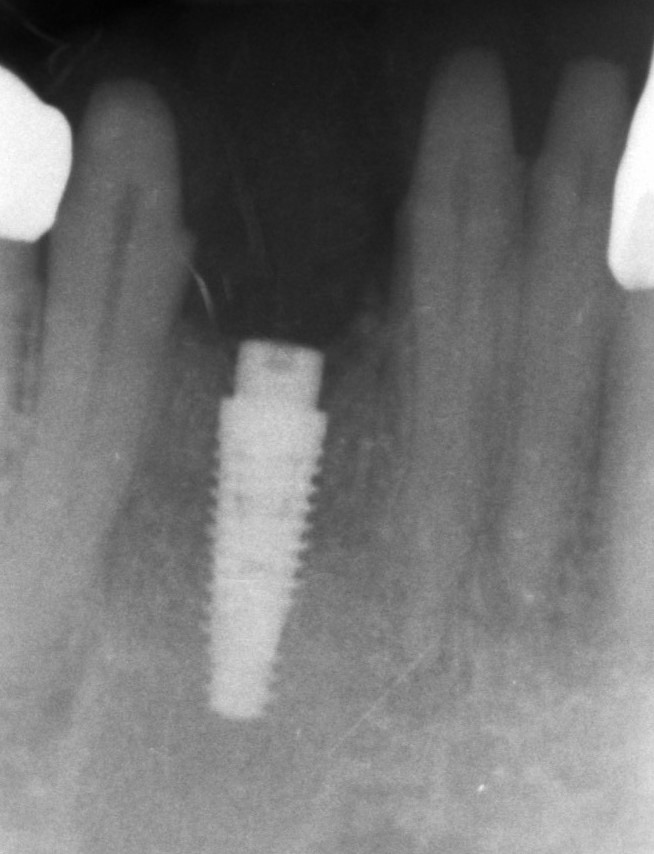

Pan Antonii z Katowic zgłosił się z prośbą o metamorfozę uśmiechu w trakcie diagnostyki w dentestica Katowice okazało się, że jednym z problemów Pana Antoniego jest zatrzymana dolna trójka. Po niezbędnej diagnostyce usunięto z kości zatrzymany ząb i jednocześnie zregenerowano ubytek kostny po zębie pozyskanym ze zmielenia tego zęba biomateriałem (w specjalnej procedurze, młynek – Liberdent), wspomagając gojenie pozyskaną z krwi Pacjenta autogenną fibryną bogatopłytkową (PRF), dzięki takiemu postępowaniu utworzono stabilne podłoże pod przyszły implant, a używając materiałów autogennych zminimalizowano ryzyko. Kolejnym etapem było posadowienie implantu, obecnie Pacjent oczekuje na wykonanie korony na implancie.

Do tego czasu Pacjent jest zaopatrzony mostem tymczasowym żeby zamaskować brak dolnej trójki.